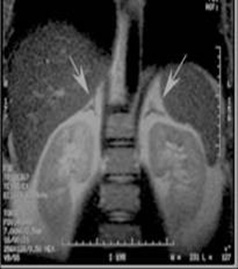

Cor T1 Dual Echo SPGR BH 3mm 0.5mm None Diaphragm to Aortic bifurcation Abdominal wall to abdominal wall Center over adrenals. Call rad if help is needed to locate adrenals.

COR T1 3D mDixon post - - Yes Diaphragm to Aortic bifurcation Abdominal wall to abdominal wall Perform @ 3 minutes post contrast.